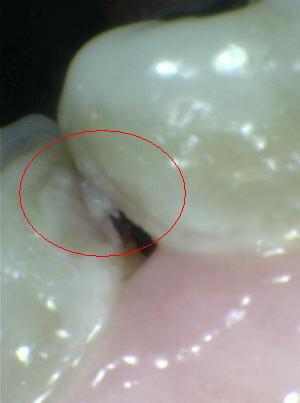

Sistema Internacional para la Detección y Evaluación de Caries (ICDAS)

¿Determine los códigos pertinentes a cada imagen?

Click en el hipervínculo: Para comparar el resultado de su diagnóstico